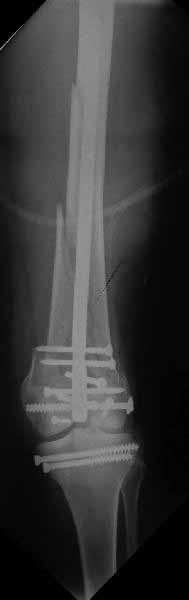

Ответ на эту часть Вашего поста – вложенный файл. Больная оперирована неделю назад по поводу открытого перелома дистального эпиметафиза бедренной кости. После операции она идёт в рентгенкабинет для выполнения послеоперационной контрольной рентгенографии, представленной на слайдах 10 и 11. Узнав, почему её фотографируют, просила передать Вам, Антон, привет.